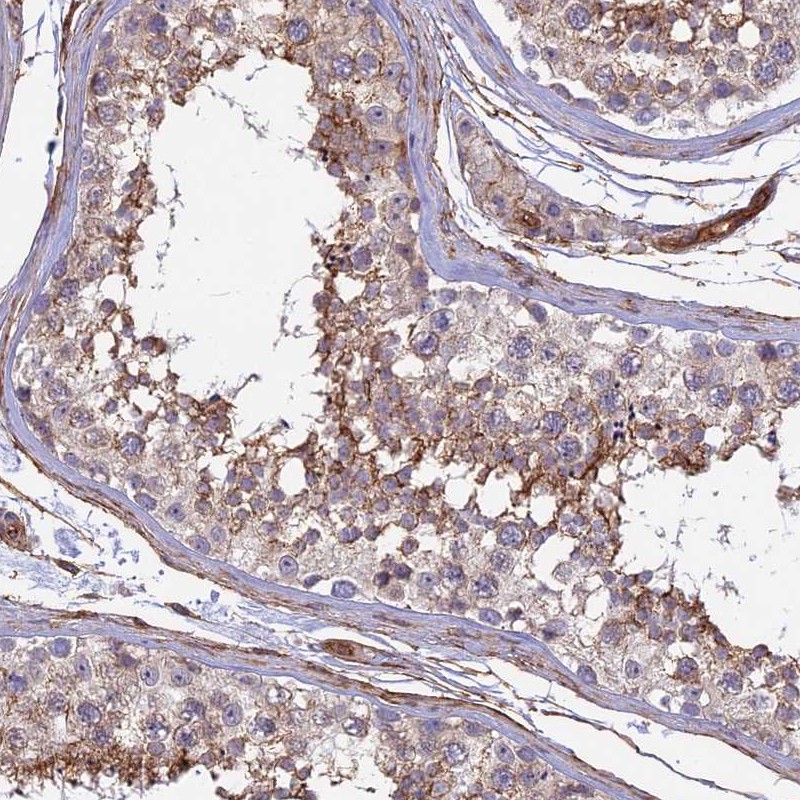

Immunohistochemical staining of human testis shows moderate cytoplasmic positivity in cells in seminiferous ducts and Leydig cells.